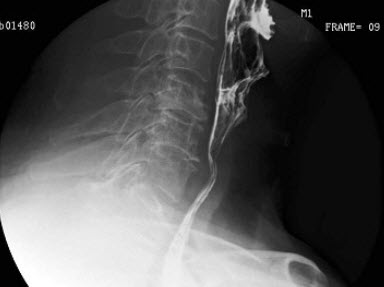

B.膜部

14、单项选择题

男,70岁,进行性吞咽困难半年,结合图像,最可能的诊断为()